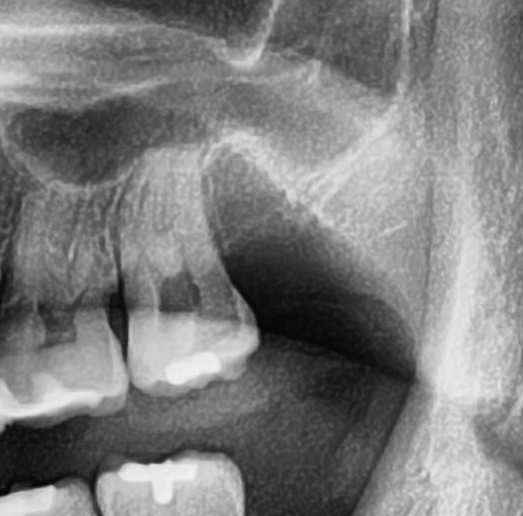

続けてパノラマ写真を撮影してみると、左上の親知らずは手前の歯と並んでまっすぐ生えているのが確認できました。

今回は上顎洞から近い距離にありますが、抜歯は可能と診断されました。